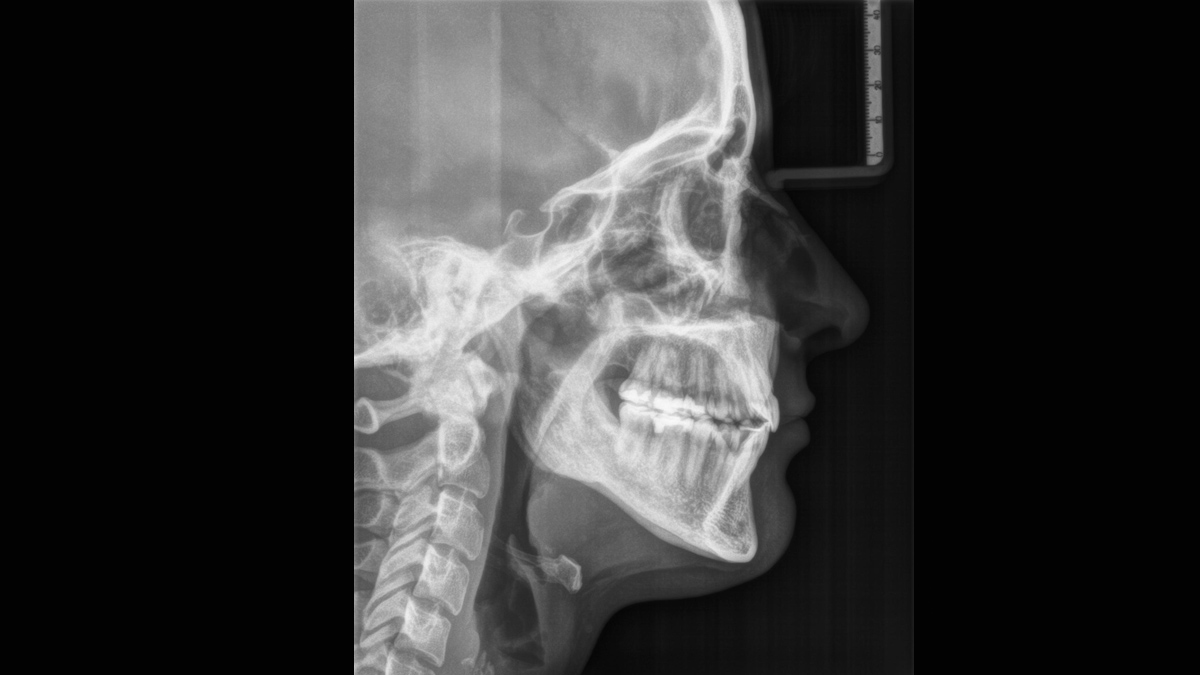

Sample Gallery of Cephalometric Images